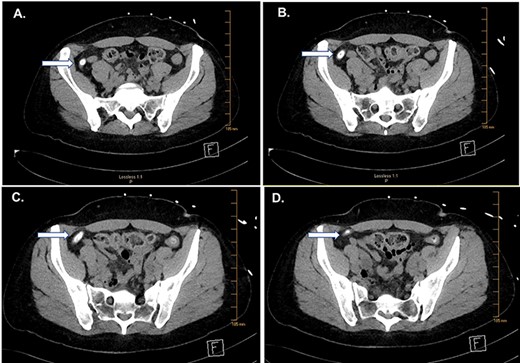

CT of the abdomen and pelvis. Serial images (A–D) from cephalad to caudal show a large fecalith (arrows).

Computed tomography (CT) imaging showed an appendix with an appendicolith with mild dilation (9 mm) and no peri-appendiceal inflammatory changes (Fig. 1). Compared to a CT scan obtained in 2013, this study showed an appendicolith with mild dilation.